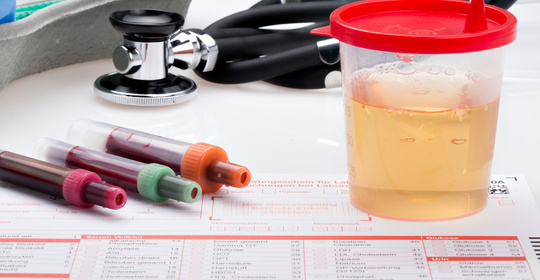

新生兒貧血:就診科室及處理措施